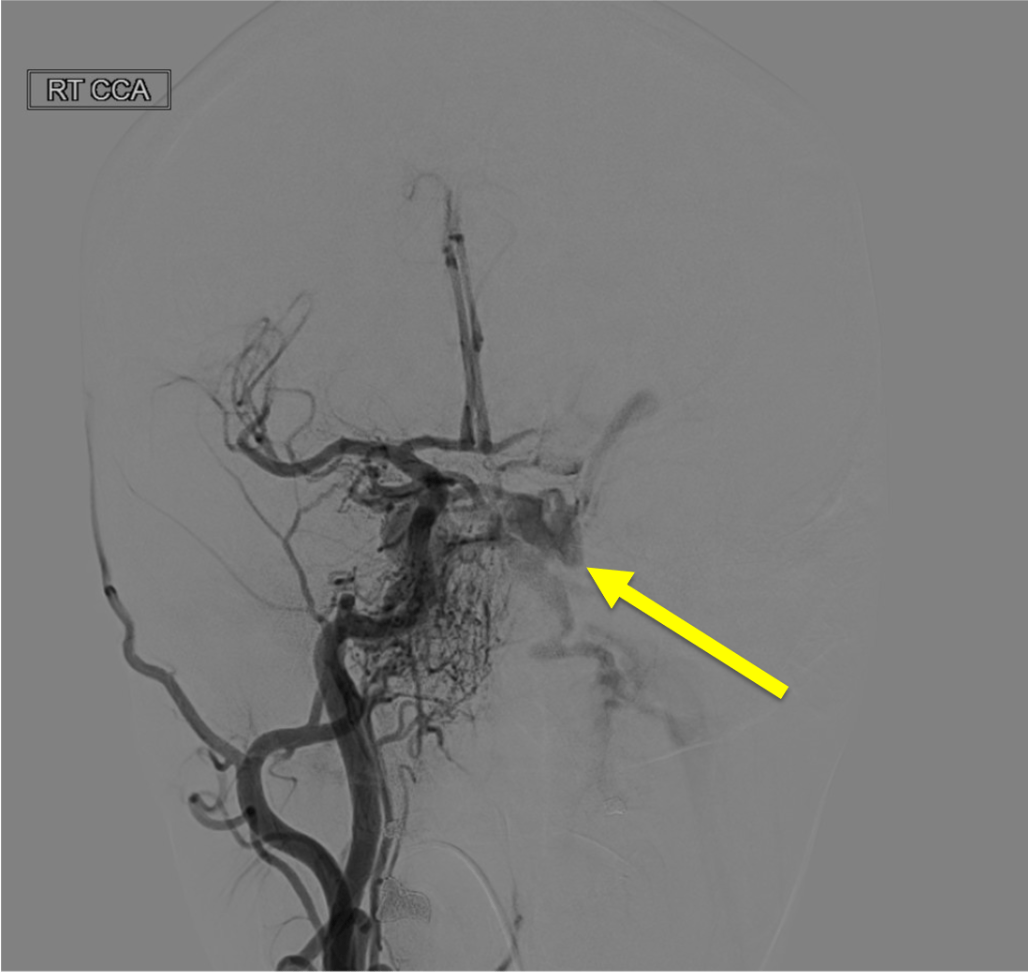

Pathologic early filling of this structure is seen on this AP view of the R CCA injection:

Cavernous sinus